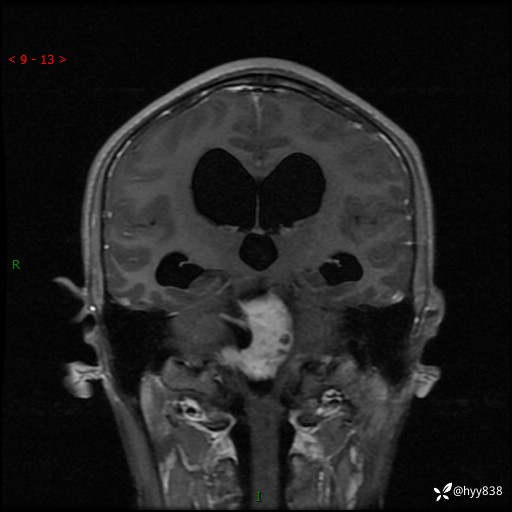

性别:男

年龄:17岁

简要病史:头痛伴间断性呕吐1月余,外院CT提示颅脑占位

颅脑MRI平扫+增强